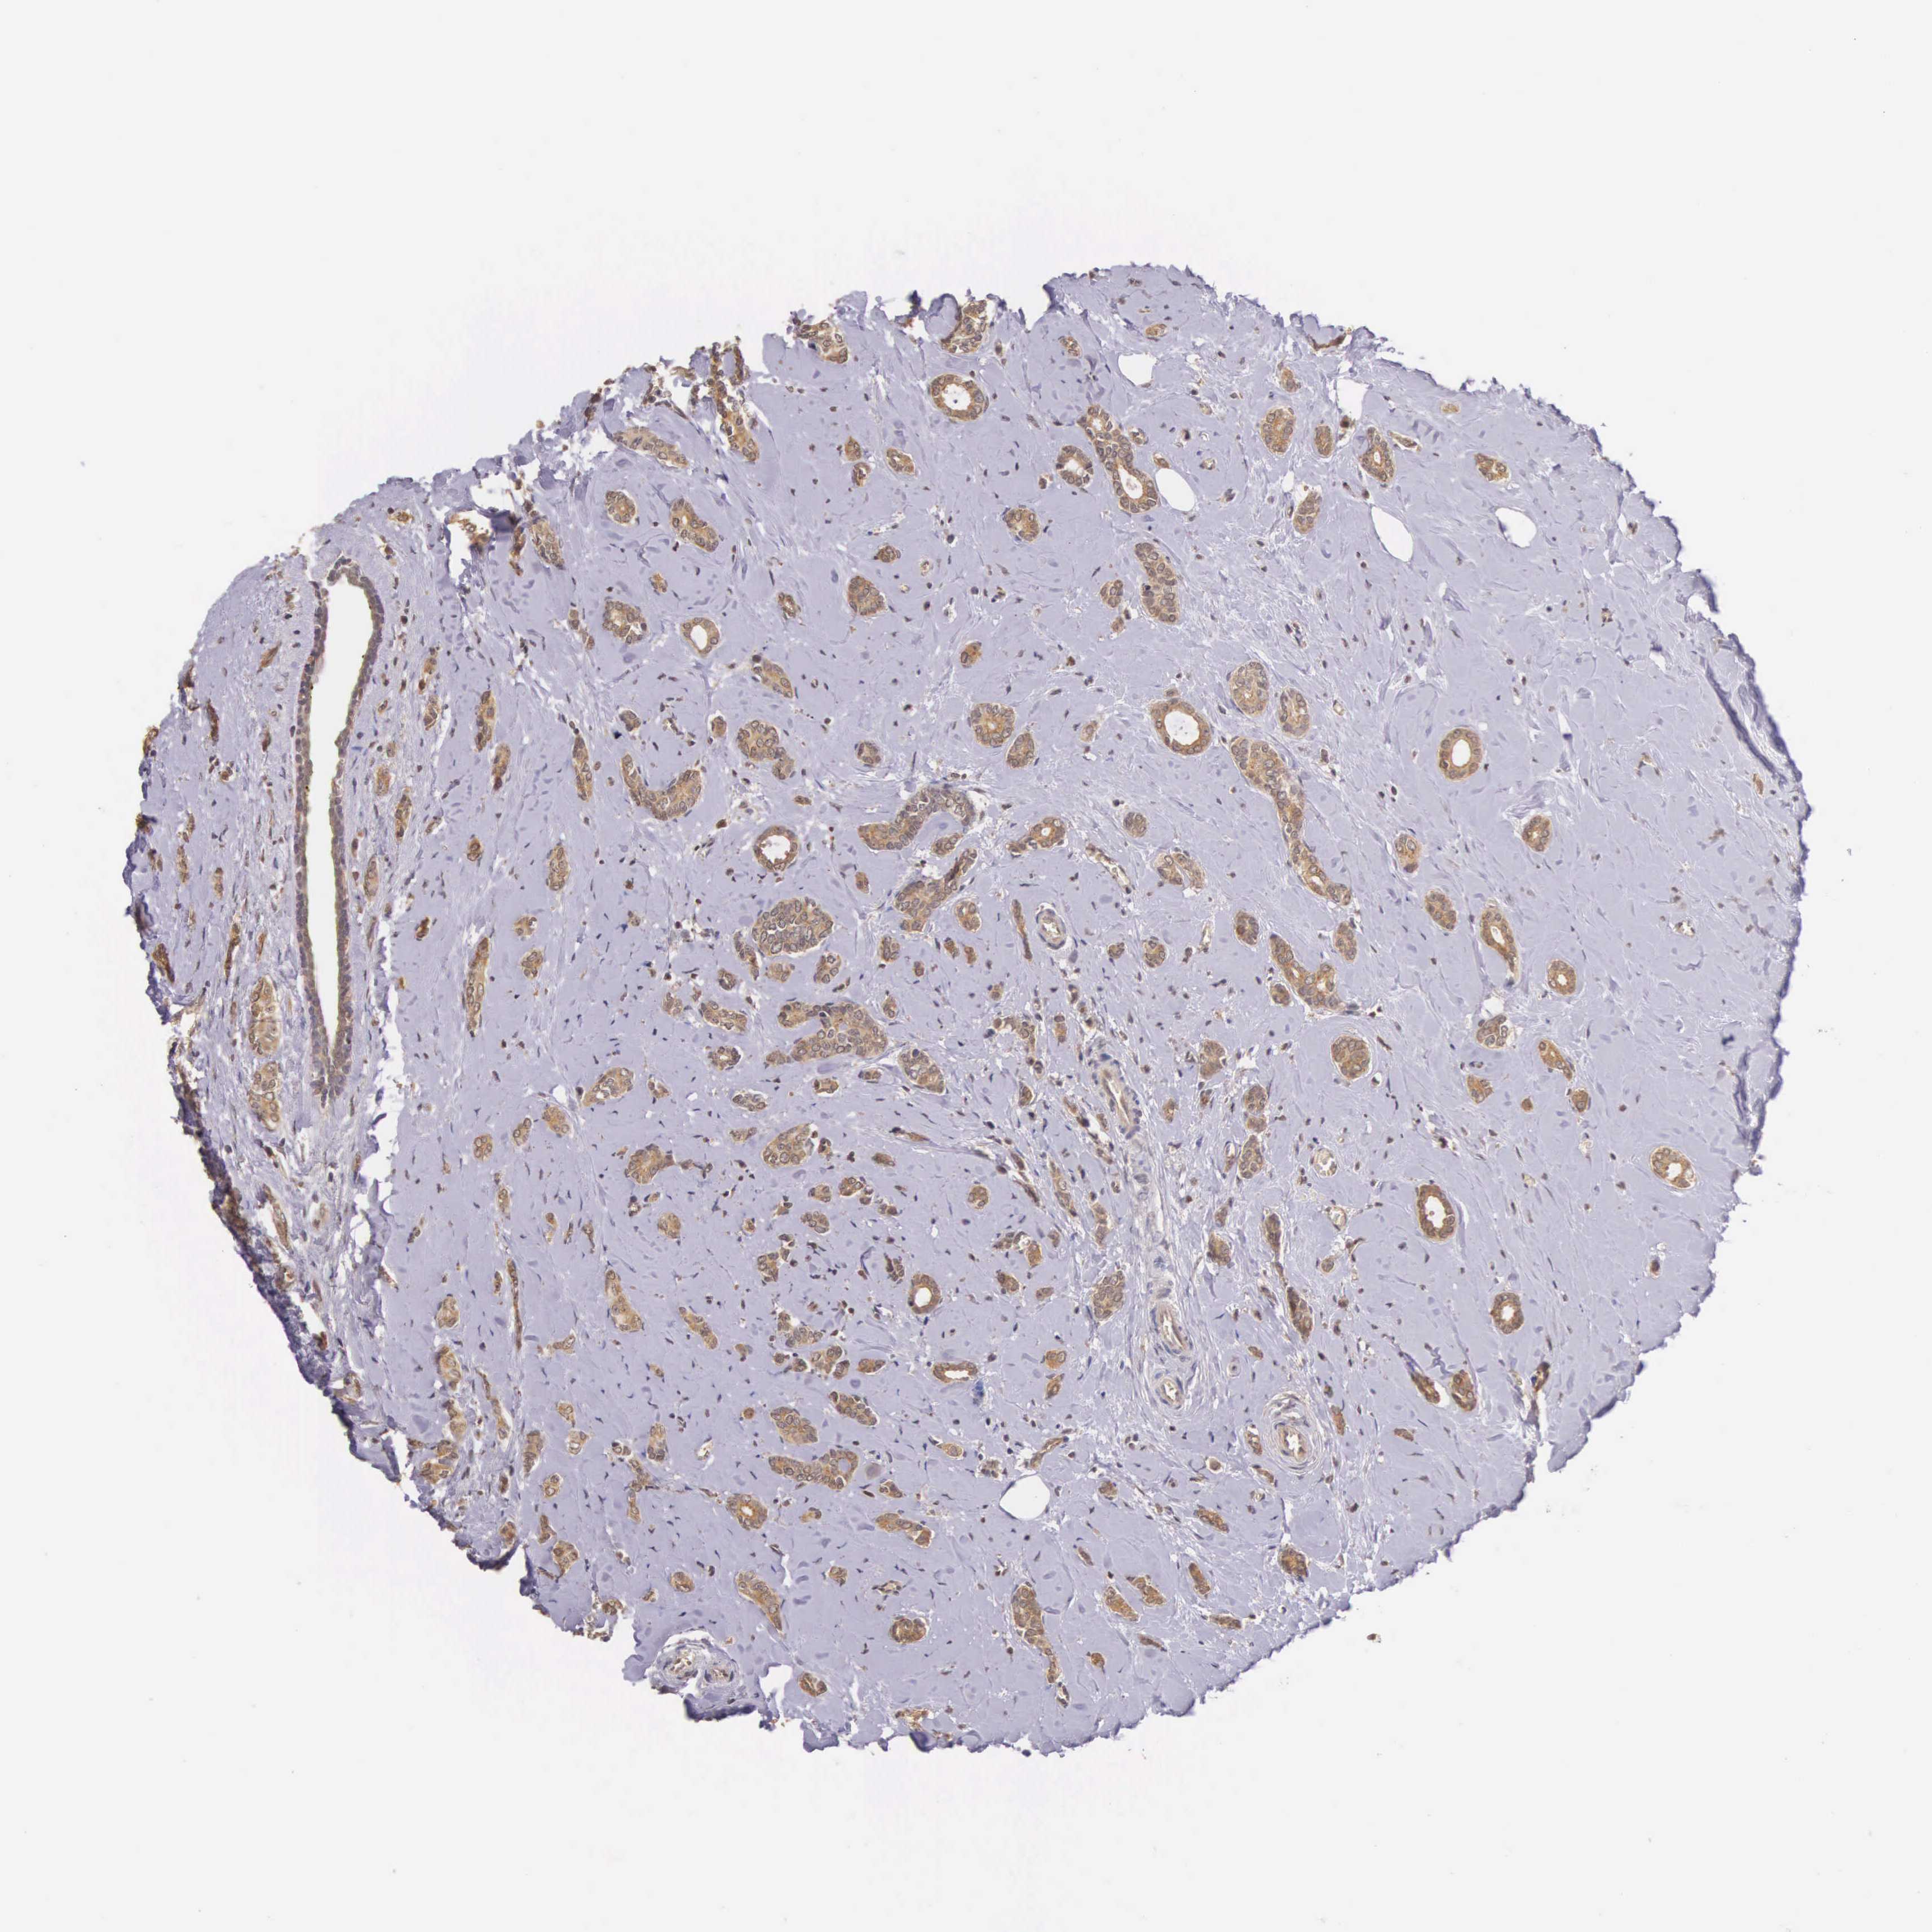

CANCER BREAST CANCER Show tissue menu

BRCA TCGA BRCA VALIDATION PROTEIN EXPRESSION

Breast cancer

Human cancer

VASH1 is not prognostic in Breast Invasive Carcinoma (TCGA)